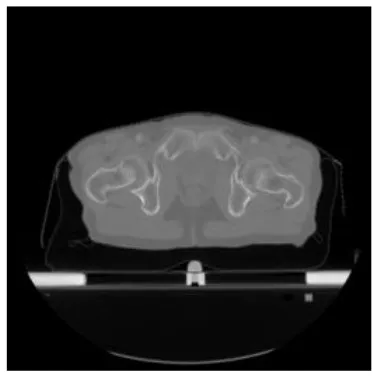

According to the acquired model parameters mentioned above, the testing set was calculated and examined. The performance of the modified algorithm for automatic organ segmentation in CT images is shown in Table 1. The organ contours segmented automatically by the algorithm were similar to those delineated by physicians manually. The model parameters including DSC, Accuracy, Recall, and Precision evaluation ones were served to evaluate the segmentation effectiveness of each organ in the validation and testing sets. In our work, the BCDU-Net CNN algorithm model was used to automatically segment different organs with the different training parameters such as epoch learning rate. The CT images which were randomly selected from the patients were put into the network model for training, and then the contours of different organs which were delineated automatically by the AI technology and manually by medical doctors were evaluated with the similarity coefficients, respectively. The results are given in Table 2. Most of the DSC values were better than 0.85 and among them the best even reached up to 0.9676. Generally, the automatic segmentation results met the requirements of clinical practice.

| Input CT image | Organs with manual segmentation | Organ with automatic segmentation | |

| Bladder | ![]() | ![]() | ![]() |

| Brainstem | ![]() | ![]() | ![]() |

| Eye-L | ![]() | ![]() | ![]() |

| Eye-R | ![]() | ![]() | ![]() |

| Femur-L | ![]() | ![]() | ![]() |

| Femur-R | ![]() | ![]() | ![]() |

| Heart | ![]() | ![]() | ![]() |

| Intestine | ![]() | ![]() | ![]() |

| Kidney-L | ![]() | ![]() | ![]() |

| Kidney-R | ![]() | ![]() | ![]() |

| Liver | ![]() | ![]() | ![]() |

| Lung-L | ![]() | ![]() | ![]() |

| Lung-R | ![]() | ![]() | ![]() |

| Mandible | ![]() | ![]() | ![]() |

| Rectum | ![]() | ![]() | ![]() |

| Spleen | ![]() | ![]() | ![]() |

| Stomach | ![]() | ![]() | ![]() |

The result of manual and automatic organ segmentation.